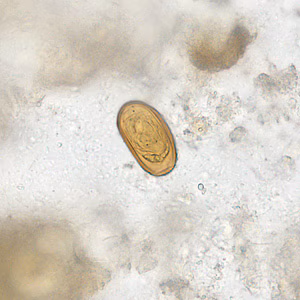

Dicrocoelium dendriticum eggs in wet mounts.

Diagnosis is based on microscopic identification of eggs in the stool, duodenal, and/or bile fluid. Note that eggs may be detected in stool following consumption of liver infected with adult flukes; additional specimens should be collected to distinguish this spurious passage from a true infection. Adult flukes are rarely recovered.